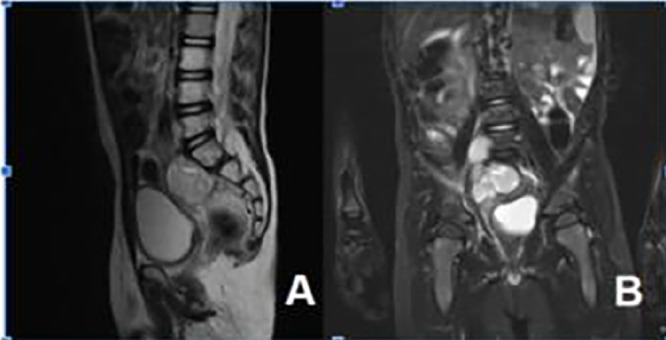

Abstract Image